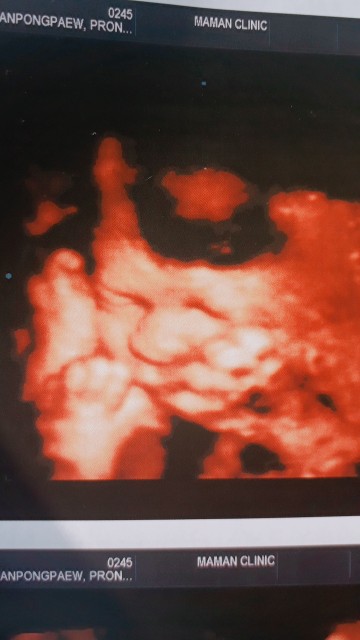

ขอดูรูปซาวของแม่ๆหน่อยค้าว่าได้ผู้หญิงผู้ชาย บ้านนี้ผู้ชายจ้าา

ญ จ้า

จมูก